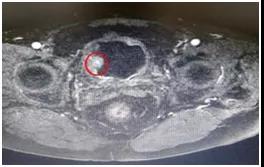

MRI显示膀胱内多发肿瘤

患者系男性73岁高龄,因反复尿频、尿急、尿痛伴有肉眼血尿半年来我院就诊,入院后MRI显示膀胱多发肿瘤(上图),术前膀胱镜检查,提示高级别尿路上皮癌。